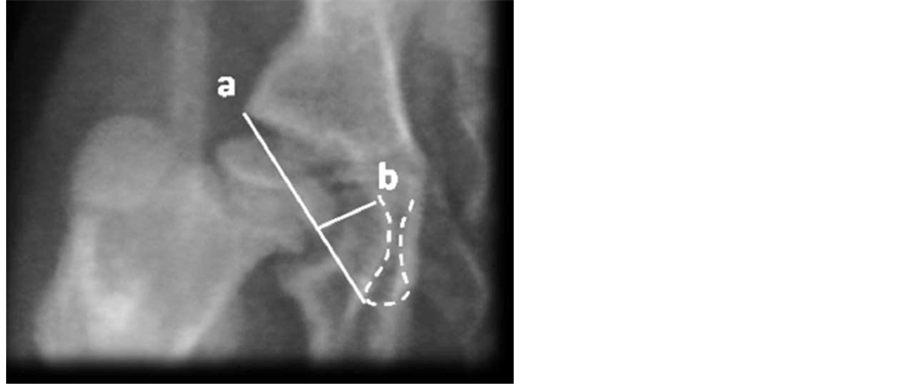

The following parameters were compared between groups: ADI [15] , CE angle of Wiberg, AS and Acetabular anteversion (AA) (Figure 6(a) and Figure 6(b)).

Figure 6. Acetabular antevertion (AA). It’s measured in the true a-p, given by an angle taken from the inferior edge of the acetabulum drawing two vectors which directions are: the first one goes until the medial notch that corresponds to the ending of the anterior wall; the second vector goes until the superior-external edge of the acetabulum (n: 12 degrees). (a) Measured in 3D-CT, (b) Measured in CT scan.